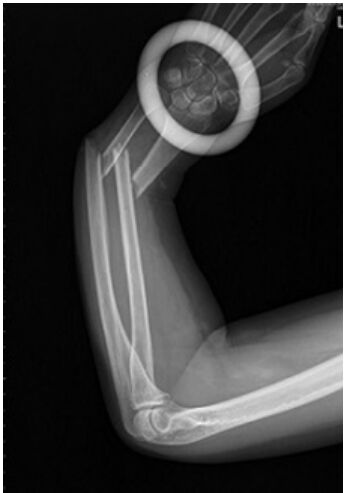

49.57 歲女性今日左手遭到墜落花盆壓到,左手前臂腫脹瘀青變形,X 光如附圖所示,下列敘述何項正確?①X 光顯示左手橈骨幹與尺骨幹骨折 ②該骨折機轉較常為扭轉暴力造成 ③此患者骨折需優先整復橈骨 ④該 骨折成人復位後固定至臨床癒合約 4 週(A)①② (B)①③ (C)②④ (D)③④